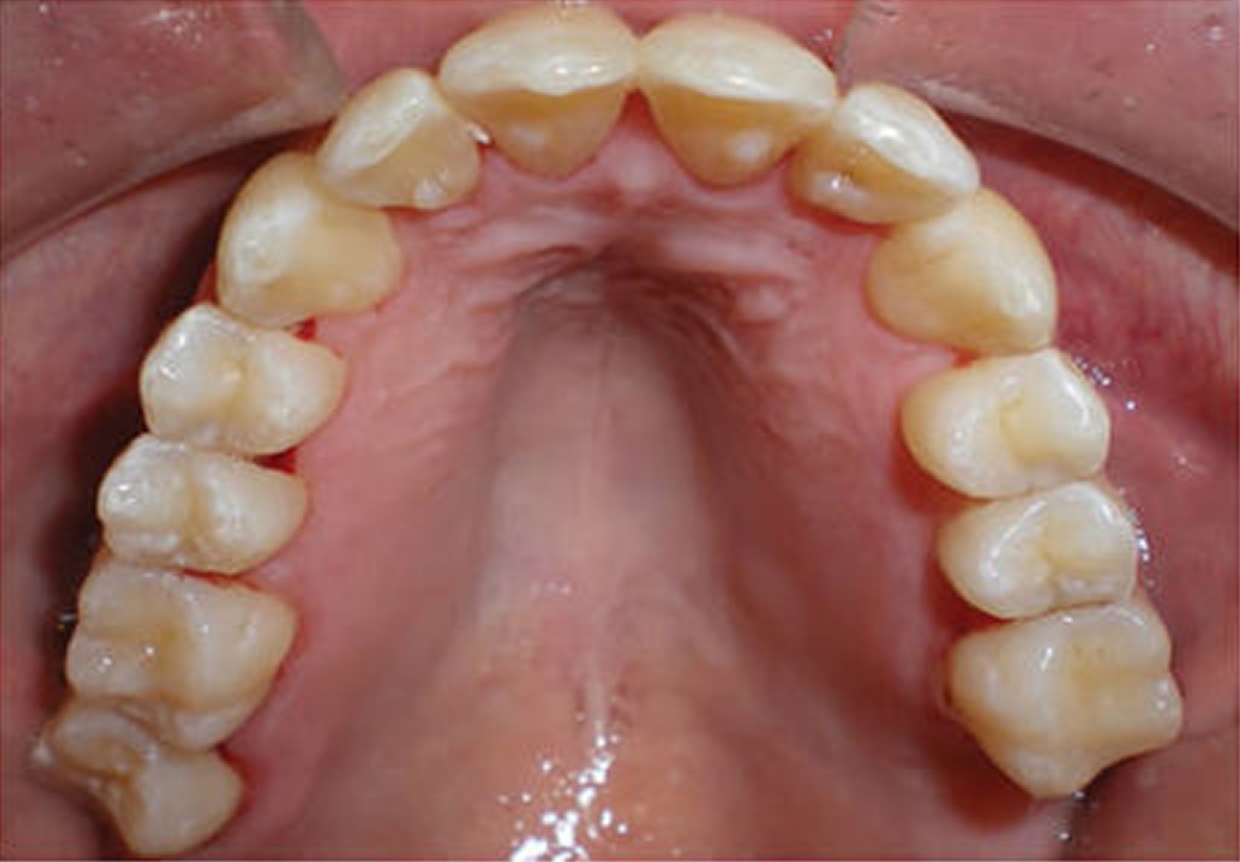

For many patients, an orthodontic intervention in Highland, NY or Ramsey, NJ can improve and sometimes eliminate these risks. Below are pictures of an OSA patient that benefitted from orthodontic treatment’s life-changing effects at Van Vliet & Ganz Orthodontics.